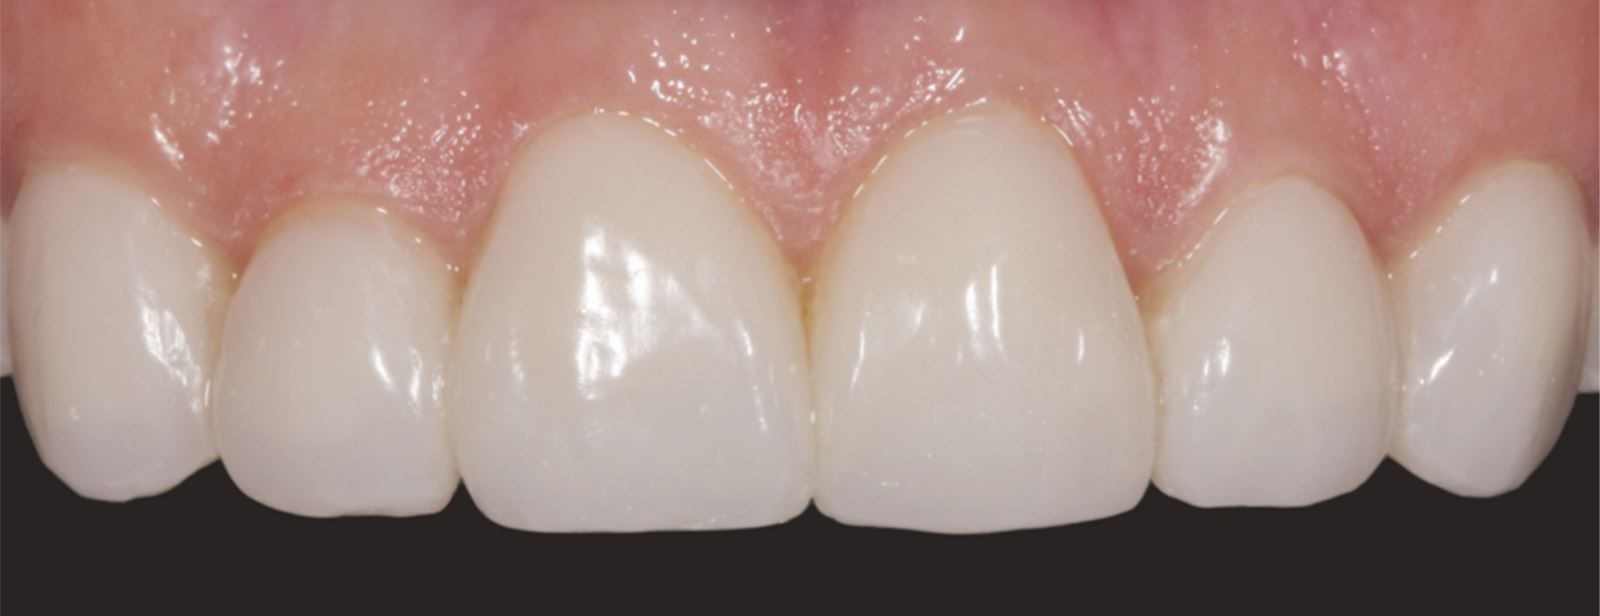

Výsledek cementace:

Finální cementace vedla ke stabilnímu a esteticky přijatelnému uložení fazet.

Výsledek a závěrečné zhodnocení

Tento postup úspěšně vyřešil estetické obavy pacientky překrytím diskolorace horních frontálních zubů a dosažením přirozeného, vyváženého vzhledu ve vztahu k dolním frontám. Použití kompozitních fazet bez preparace poskytlo konzervativní, vysoce efektivní řešení, které respektovalo finanční možnosti pacientky a její požadavek na minimálně invazivní přístup.